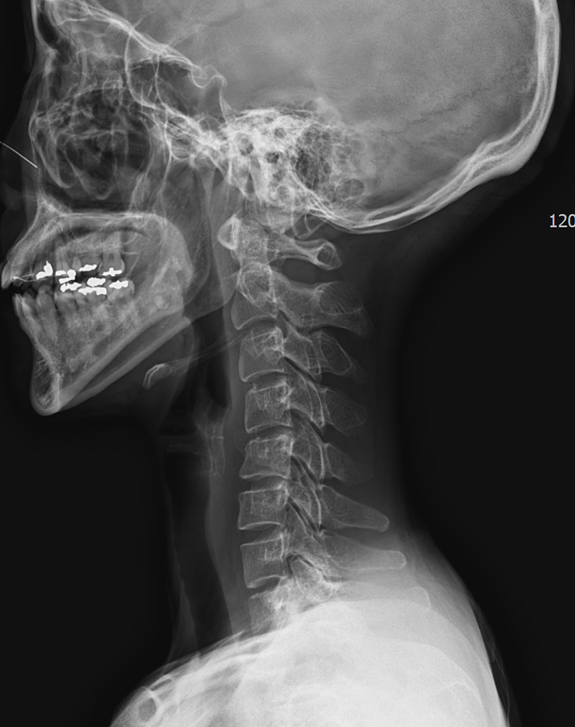

When we reviewed recent cervical X-rays from patients in our clinic, a surprising number already showed a reverse cervical curve — not just a straight neck, but a curve that bends in the opposite direction of normal.

This is no longer a simple forward head posture. It represents the final, most advanced stage of cervical alignment deformity.

A reverse curve means the cervical spine has lost its normal C-shaped lordosis and has collapsed into a kyphotic or reversed shape.

Many patients only realize the degree of their posture change when they see their own X-ray.